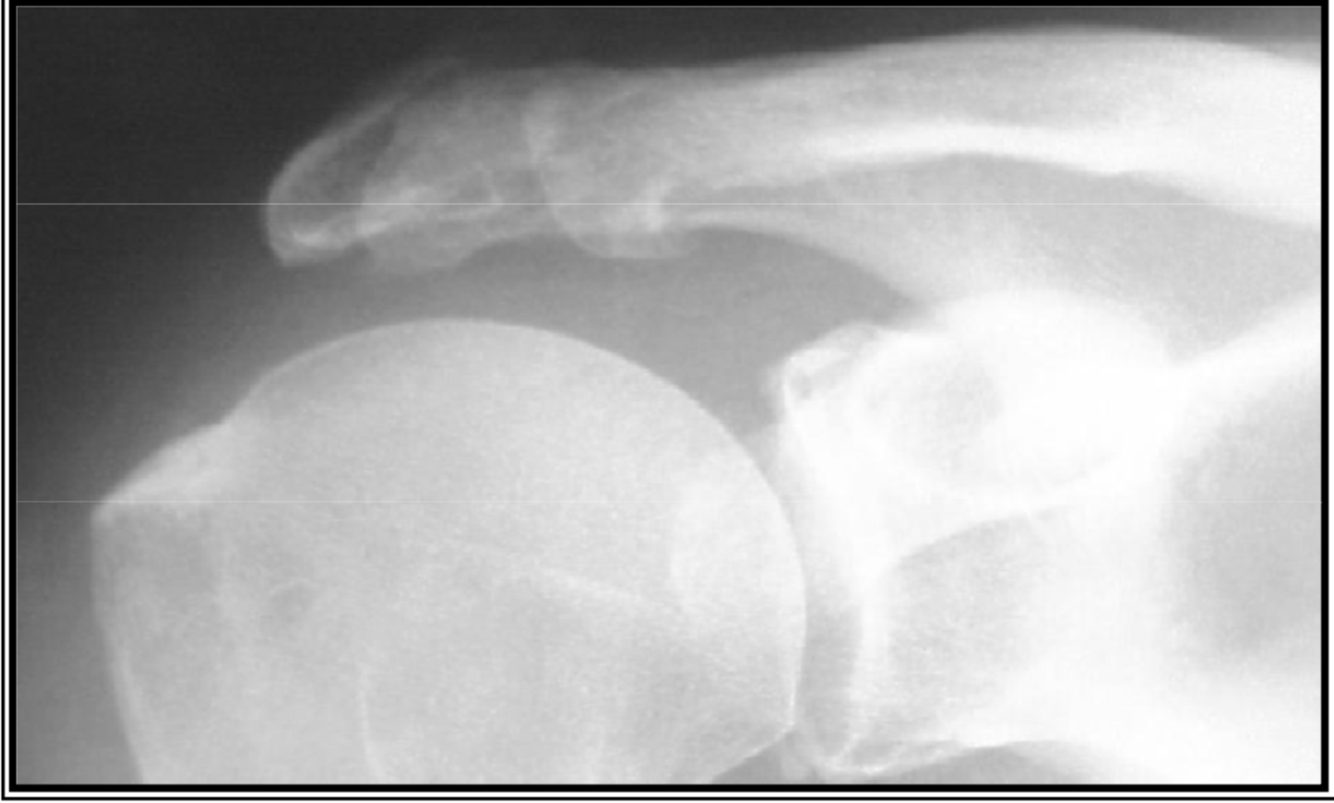

Maturation osseuse – Vues de profil

varaition anat normal